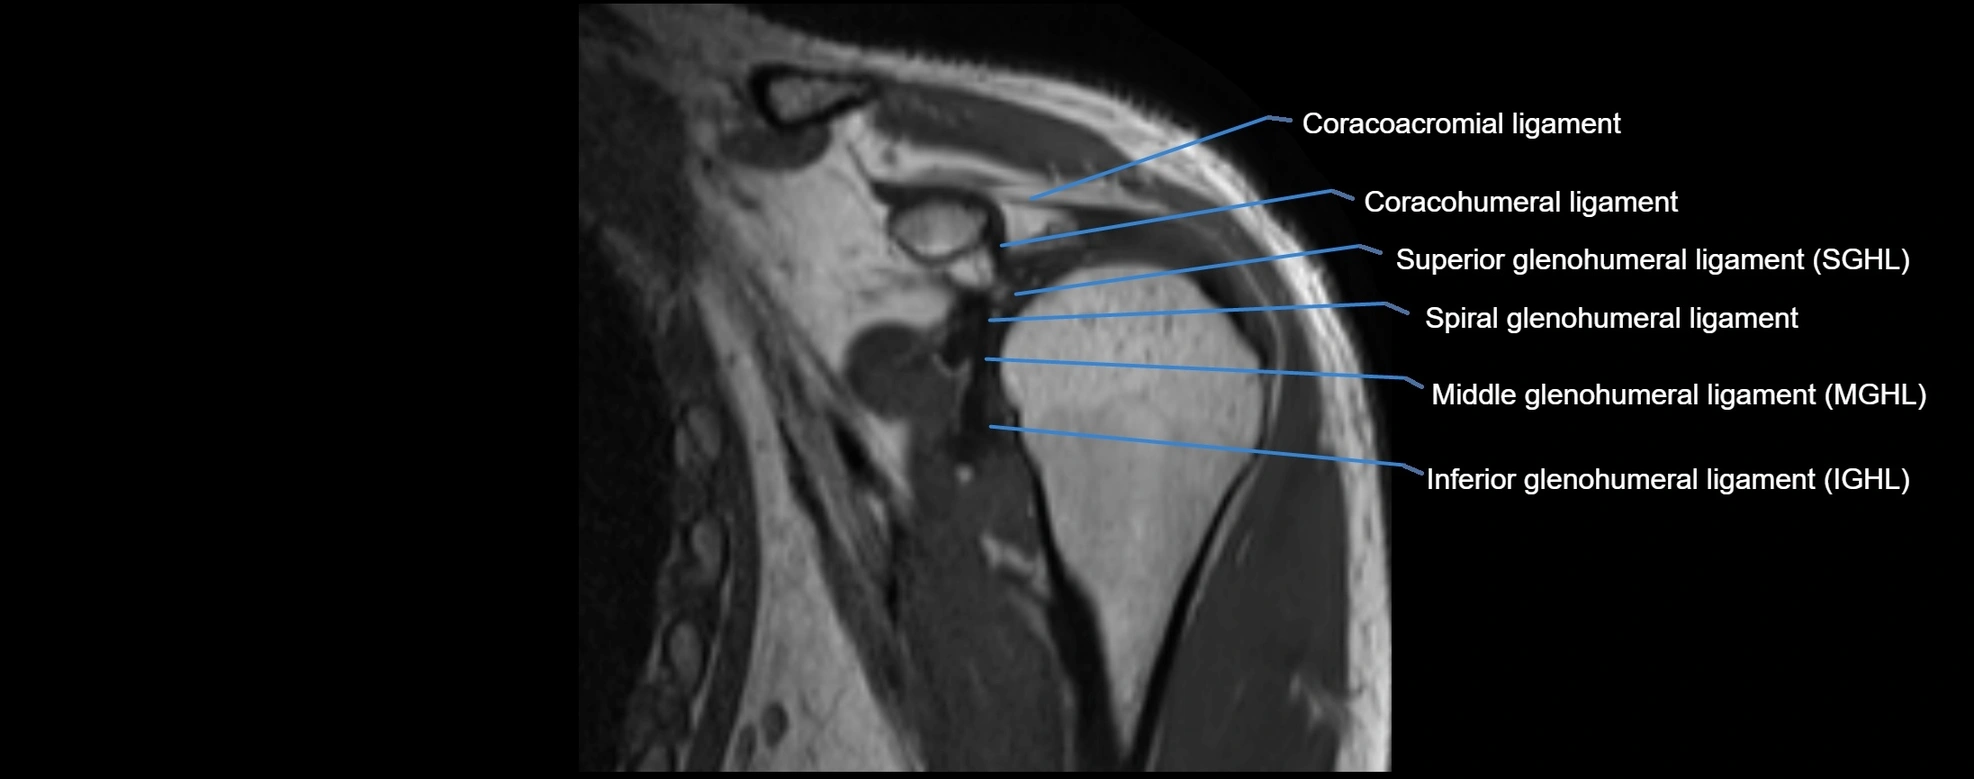

MRI images

image